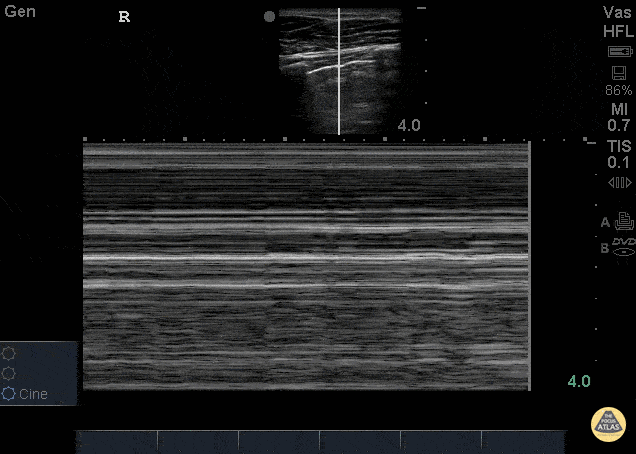

Pulmonary - Bar Code Sign - Pneumothorax

26 yo male presents to ED stating he was kicked in the chest. He went home to “try to relax and smoke some weed” now short of breath and with pleuritic chest pain after smoking. POCUS demonstrating decreased lung slide on the left. This can be seen as decreased lung sliding - In normal lungs, lung sliding refers to the parietal pleura moving against the visceral pleura - described as “ants marching.” M-mode can be used to evaluate lung sliding. Remember, normal lung slide will look like a seashore on M-mode whereas a pneumothorax will appear as horizontal lines termed Bar Code sign (pictured here). Make sure to check in the most anterior fields as well at lateral lung fields. Dr. Stacey Frisch, Dr. John F Kilpatrick - Kings County Emergency Medicine